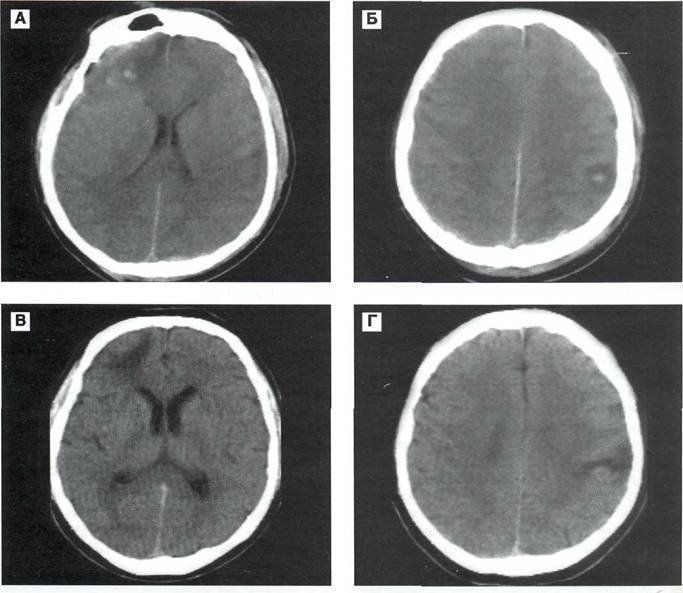

- Для диагностики тканей мозга с высокой точностью используется МРТ. Этот метод позволяет точно определить объем и распространение нарушений, а также выявить причины поражения на основе специфики расположения очагов.

Результаты МРТ

Томография позволяет определить местоположение очагов, количество погибших нейронов и степень их замещения глиальными клетками. Снимок, полученный с помощью МРТ, демонстрирует объем и расположение патологий. МРТ является одним из методов обследования головы, который помогает выявить глиоз в белом веществе лобных долей. Этот метод также позволяет установить давность нарушений, обнаружить микроангиопатию и оценить масштаб повреждений. Полученные данные помогают врачу в выборе оптимальной стратегии лечения пациента.